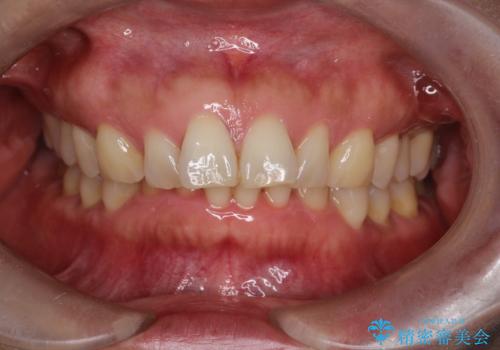

【インビザライン】出っ歯を治したい

- 前歯が出ていることを主訴に来院されました。

インビザラインにて臼歯部の遠心移動及びIPRを行なっています。

叢生量が多いケースでしたが、綺麗な歯並びとなり患者様にも満足していただきました。